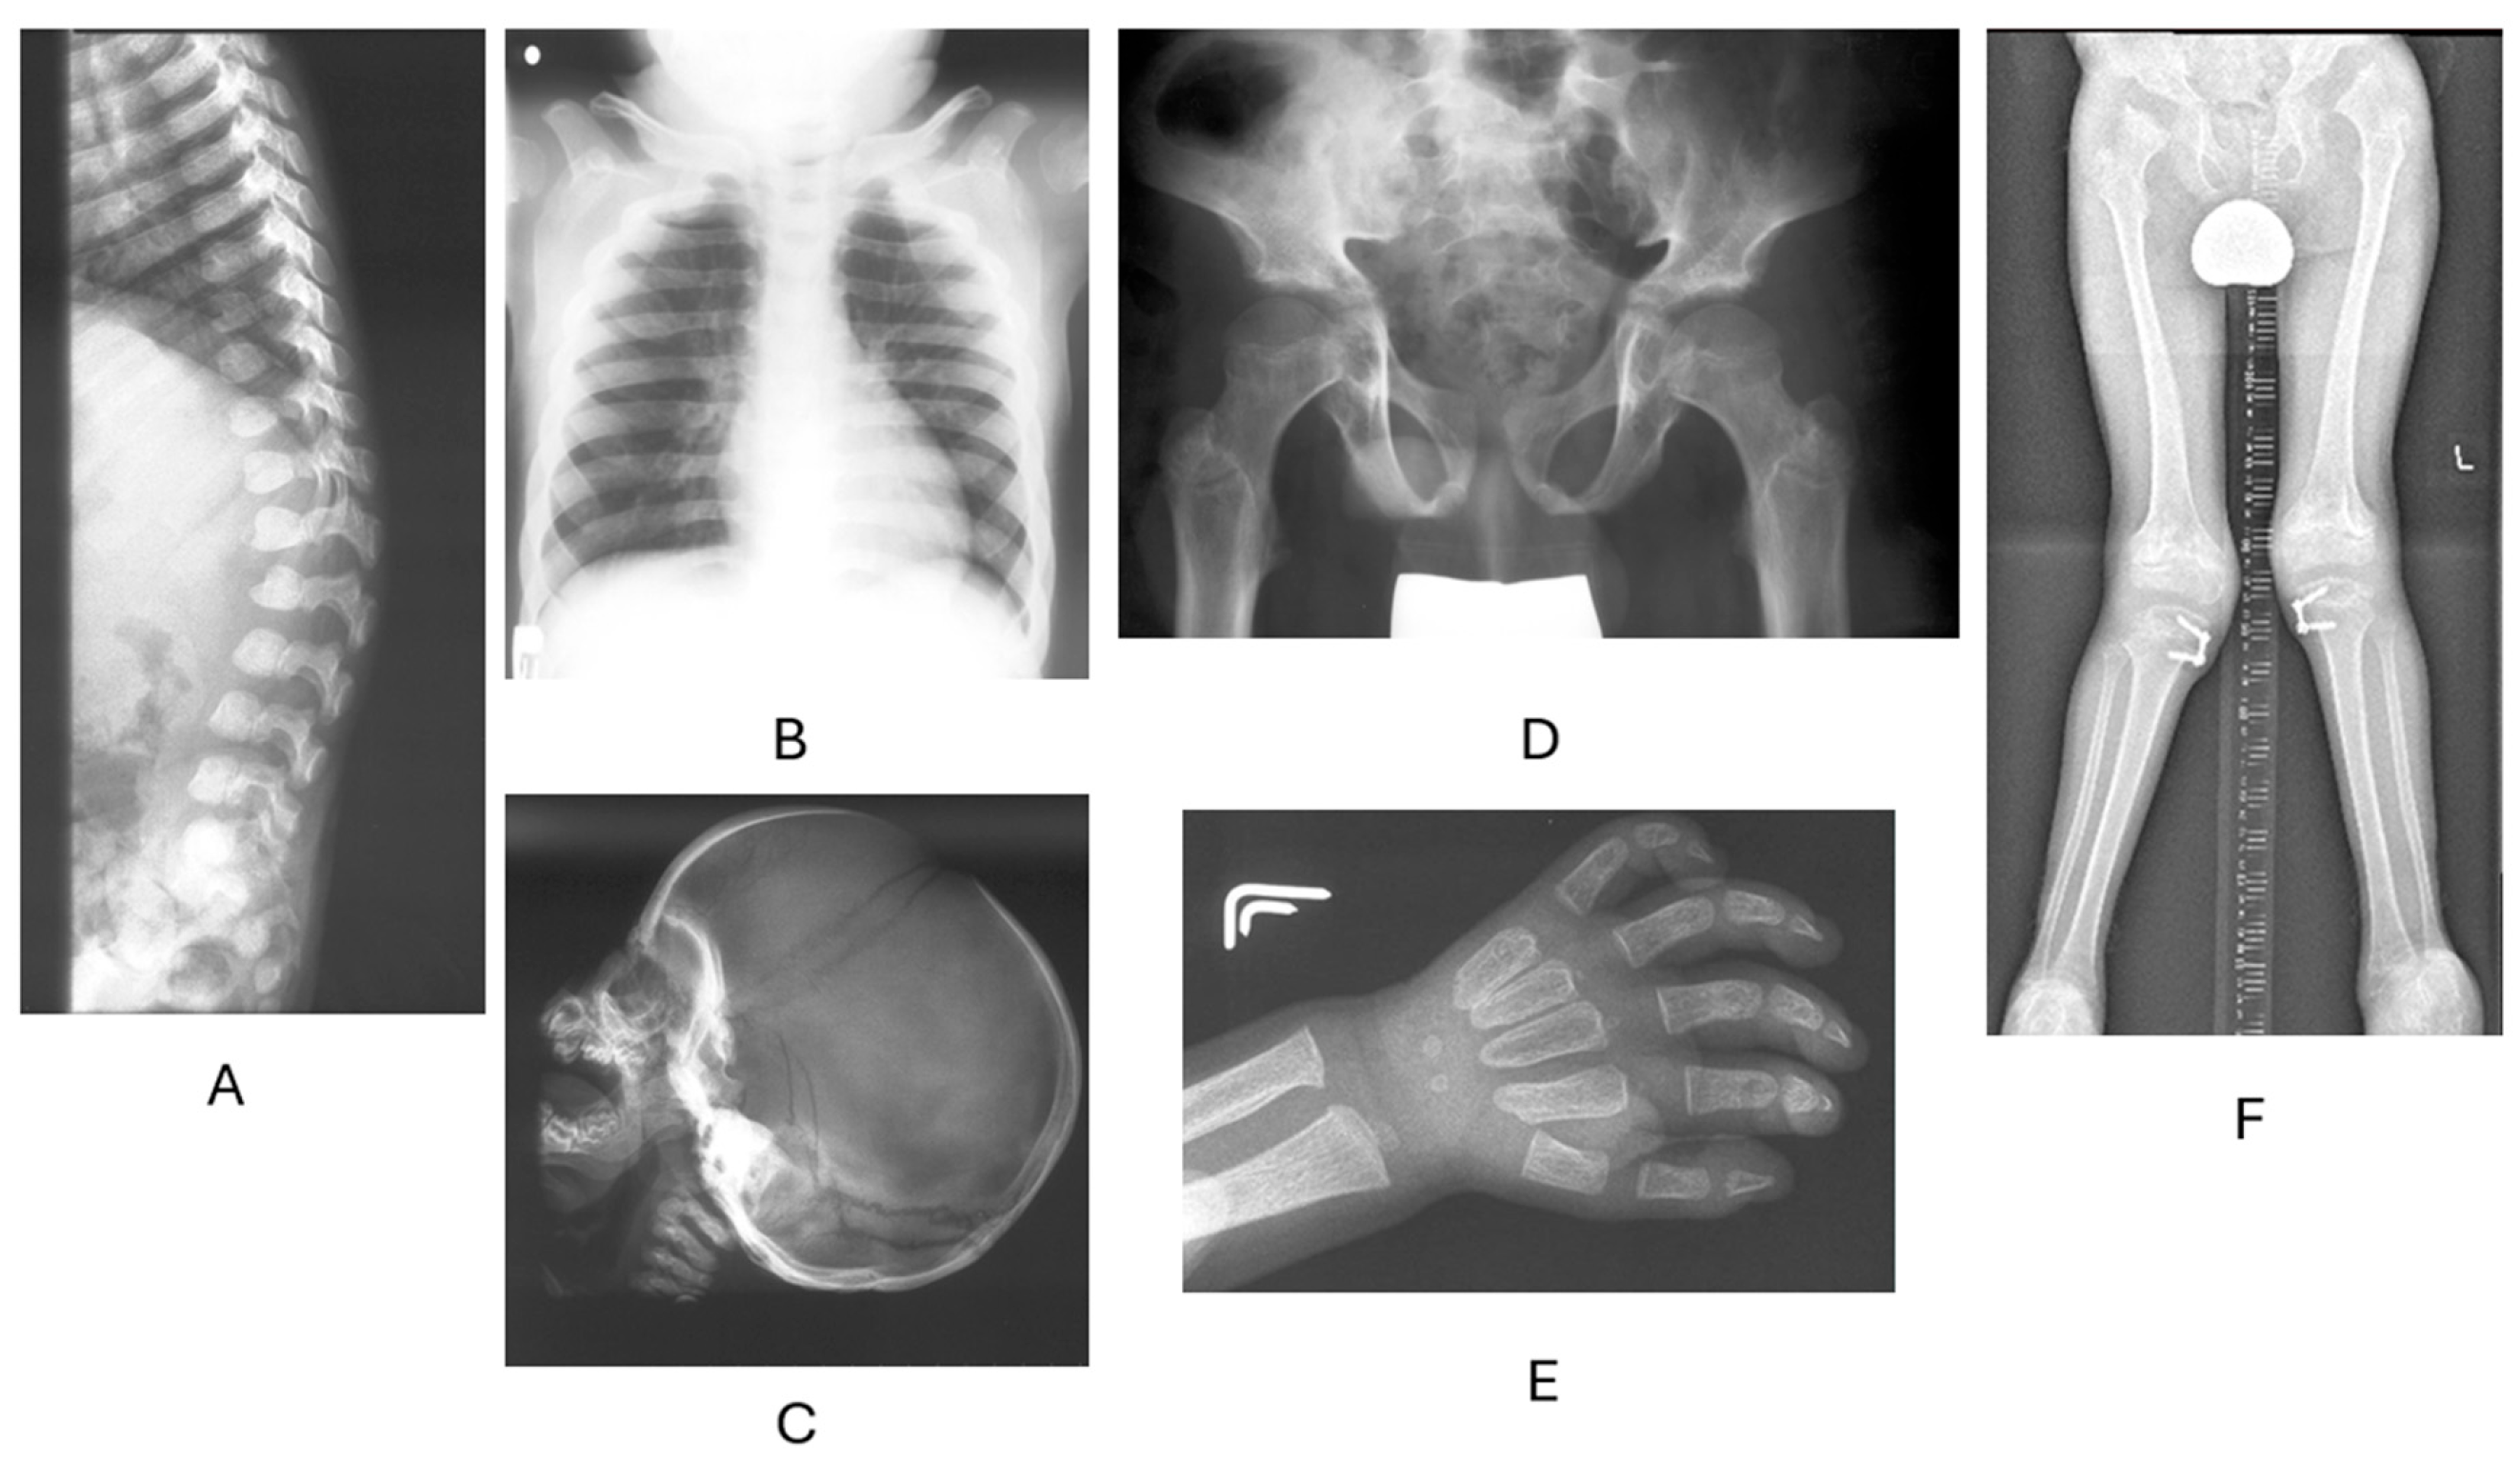

2. Biochemical, Molecular, and Cellular Disorders in MPSs

3. Clinical Manifestation of MPSs

3.1. Main Clinical Symptoms Regarding Accumulated GAGs

3.3. Skeletal Features